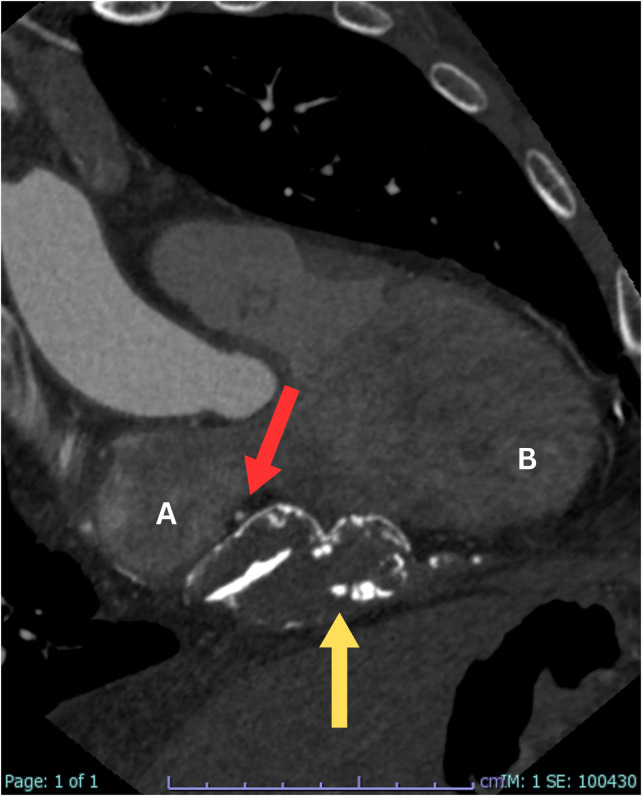

心包切除术后的显像:广泛残留的心包钙化和明显的二尖瓣增厚。

Unveiling Post-Pericardial Resection: Magnificent Imaging of Extensive Residual Pericardial Calcification and Impressive Mitral Valve Thickening.